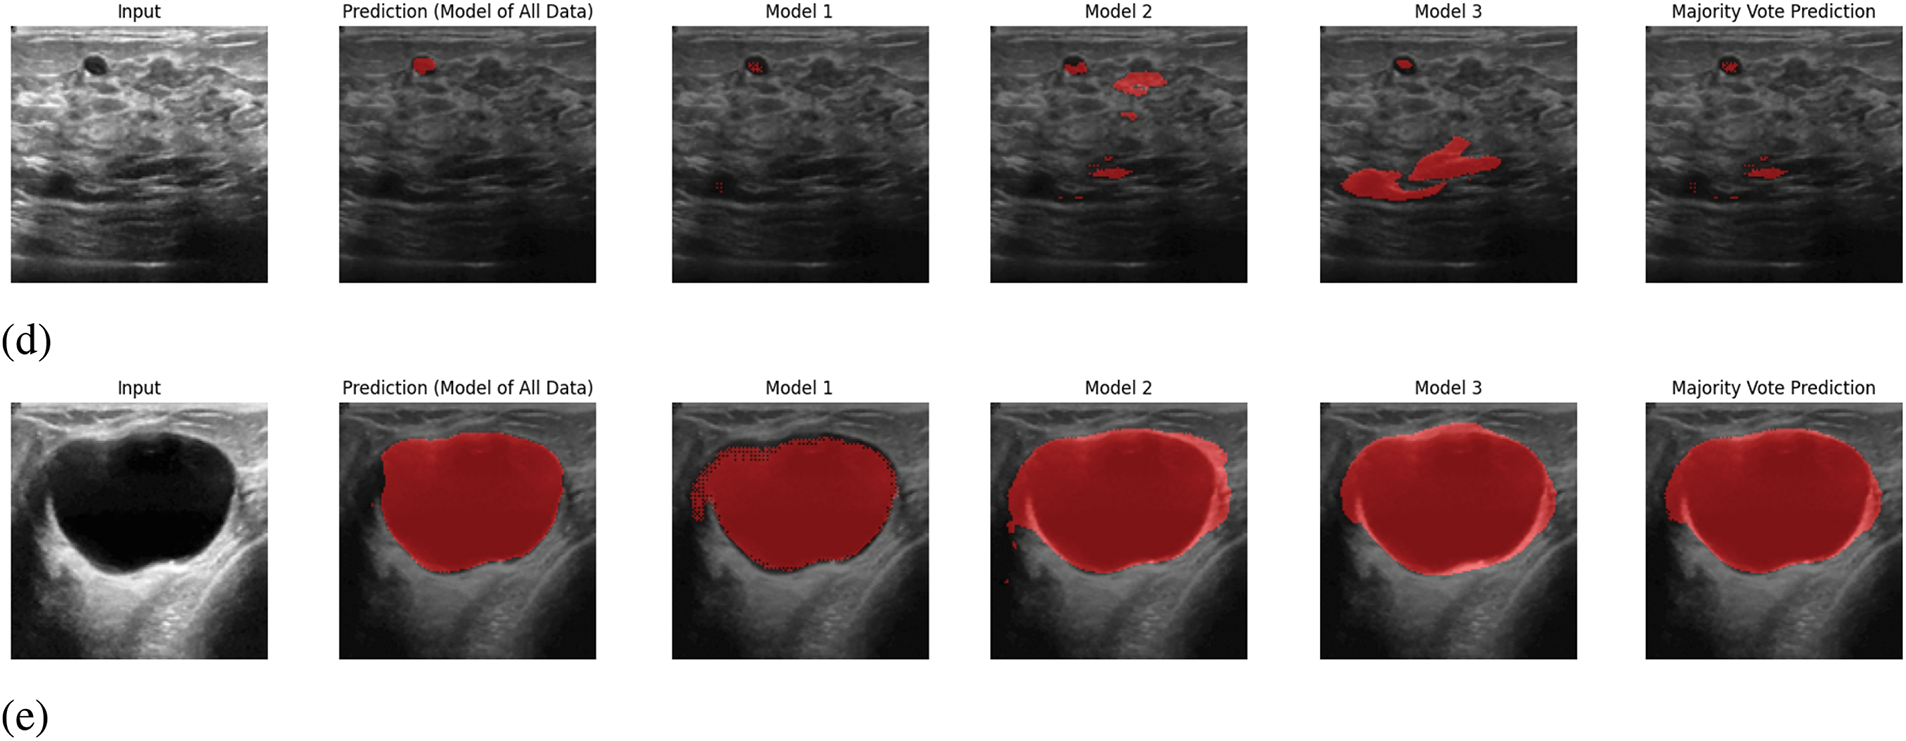

In Fig. 6, sample outputs for 5 inputs are given. In Fig. 6, along with providing the ultimate output, the predicted output from each model is also given. In the proposed system, the output will be predicted from the trained models of each segment, and the ultimate output will be selected based on pixel-wise voting majority. By looking at Fig. 6, it is visible that the ultimate output is almost similar output with the predicted output from the trained model of all data. Therefore, it can be claimed that the proposed prediction system works appropriately.

Figure 6: Sample output predictions: (a) Input 1, (b) Input 2, (c) Input 3, (d) Input 4, (e) Input 5